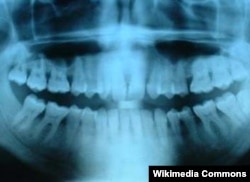

Электр заряды курт жеген тишке даба

Кыргызстанда эң көп катталган тиш ооруларынын бири – кариес. Дүйнө жүзү боюнча бул дартка жылына дээрлик эки жарым миллиард адам чалдыгат. Британияда кариести пломбасыз, оорутпай жана тишти өгөөлөбөй айыктыруунун жолу табылды.

Дүйнө калкында эң кеңири тараган тиштин дарты – кариес. Мындан жылына дүйнө боюнча эки жарым миллиард адам жабыркайт.

Кариес бир нече баскыч менен оорлошот. Биринчиден, тишти каптаган эмаль бузулганда, көзгө көрүнбөгөн жарака кетип, андан тиштеги минералдар сыртка чыга баштайт. Эгер тиш көпчүлүк минералдарын жоготсо, ал кариеске чалдыгат. Кадимки дарылоо ыкмасында "курт жеген тиш" атайын машине менен тазаланып, тиштин нервдери дарыланып, ал эми кариес баскан тиш – пломба менен жамалат. Тиштин сөөгү чирип түшүп, каналдары катуу сезгенген учурда ал тургай тишти жулдурууга туура келет.